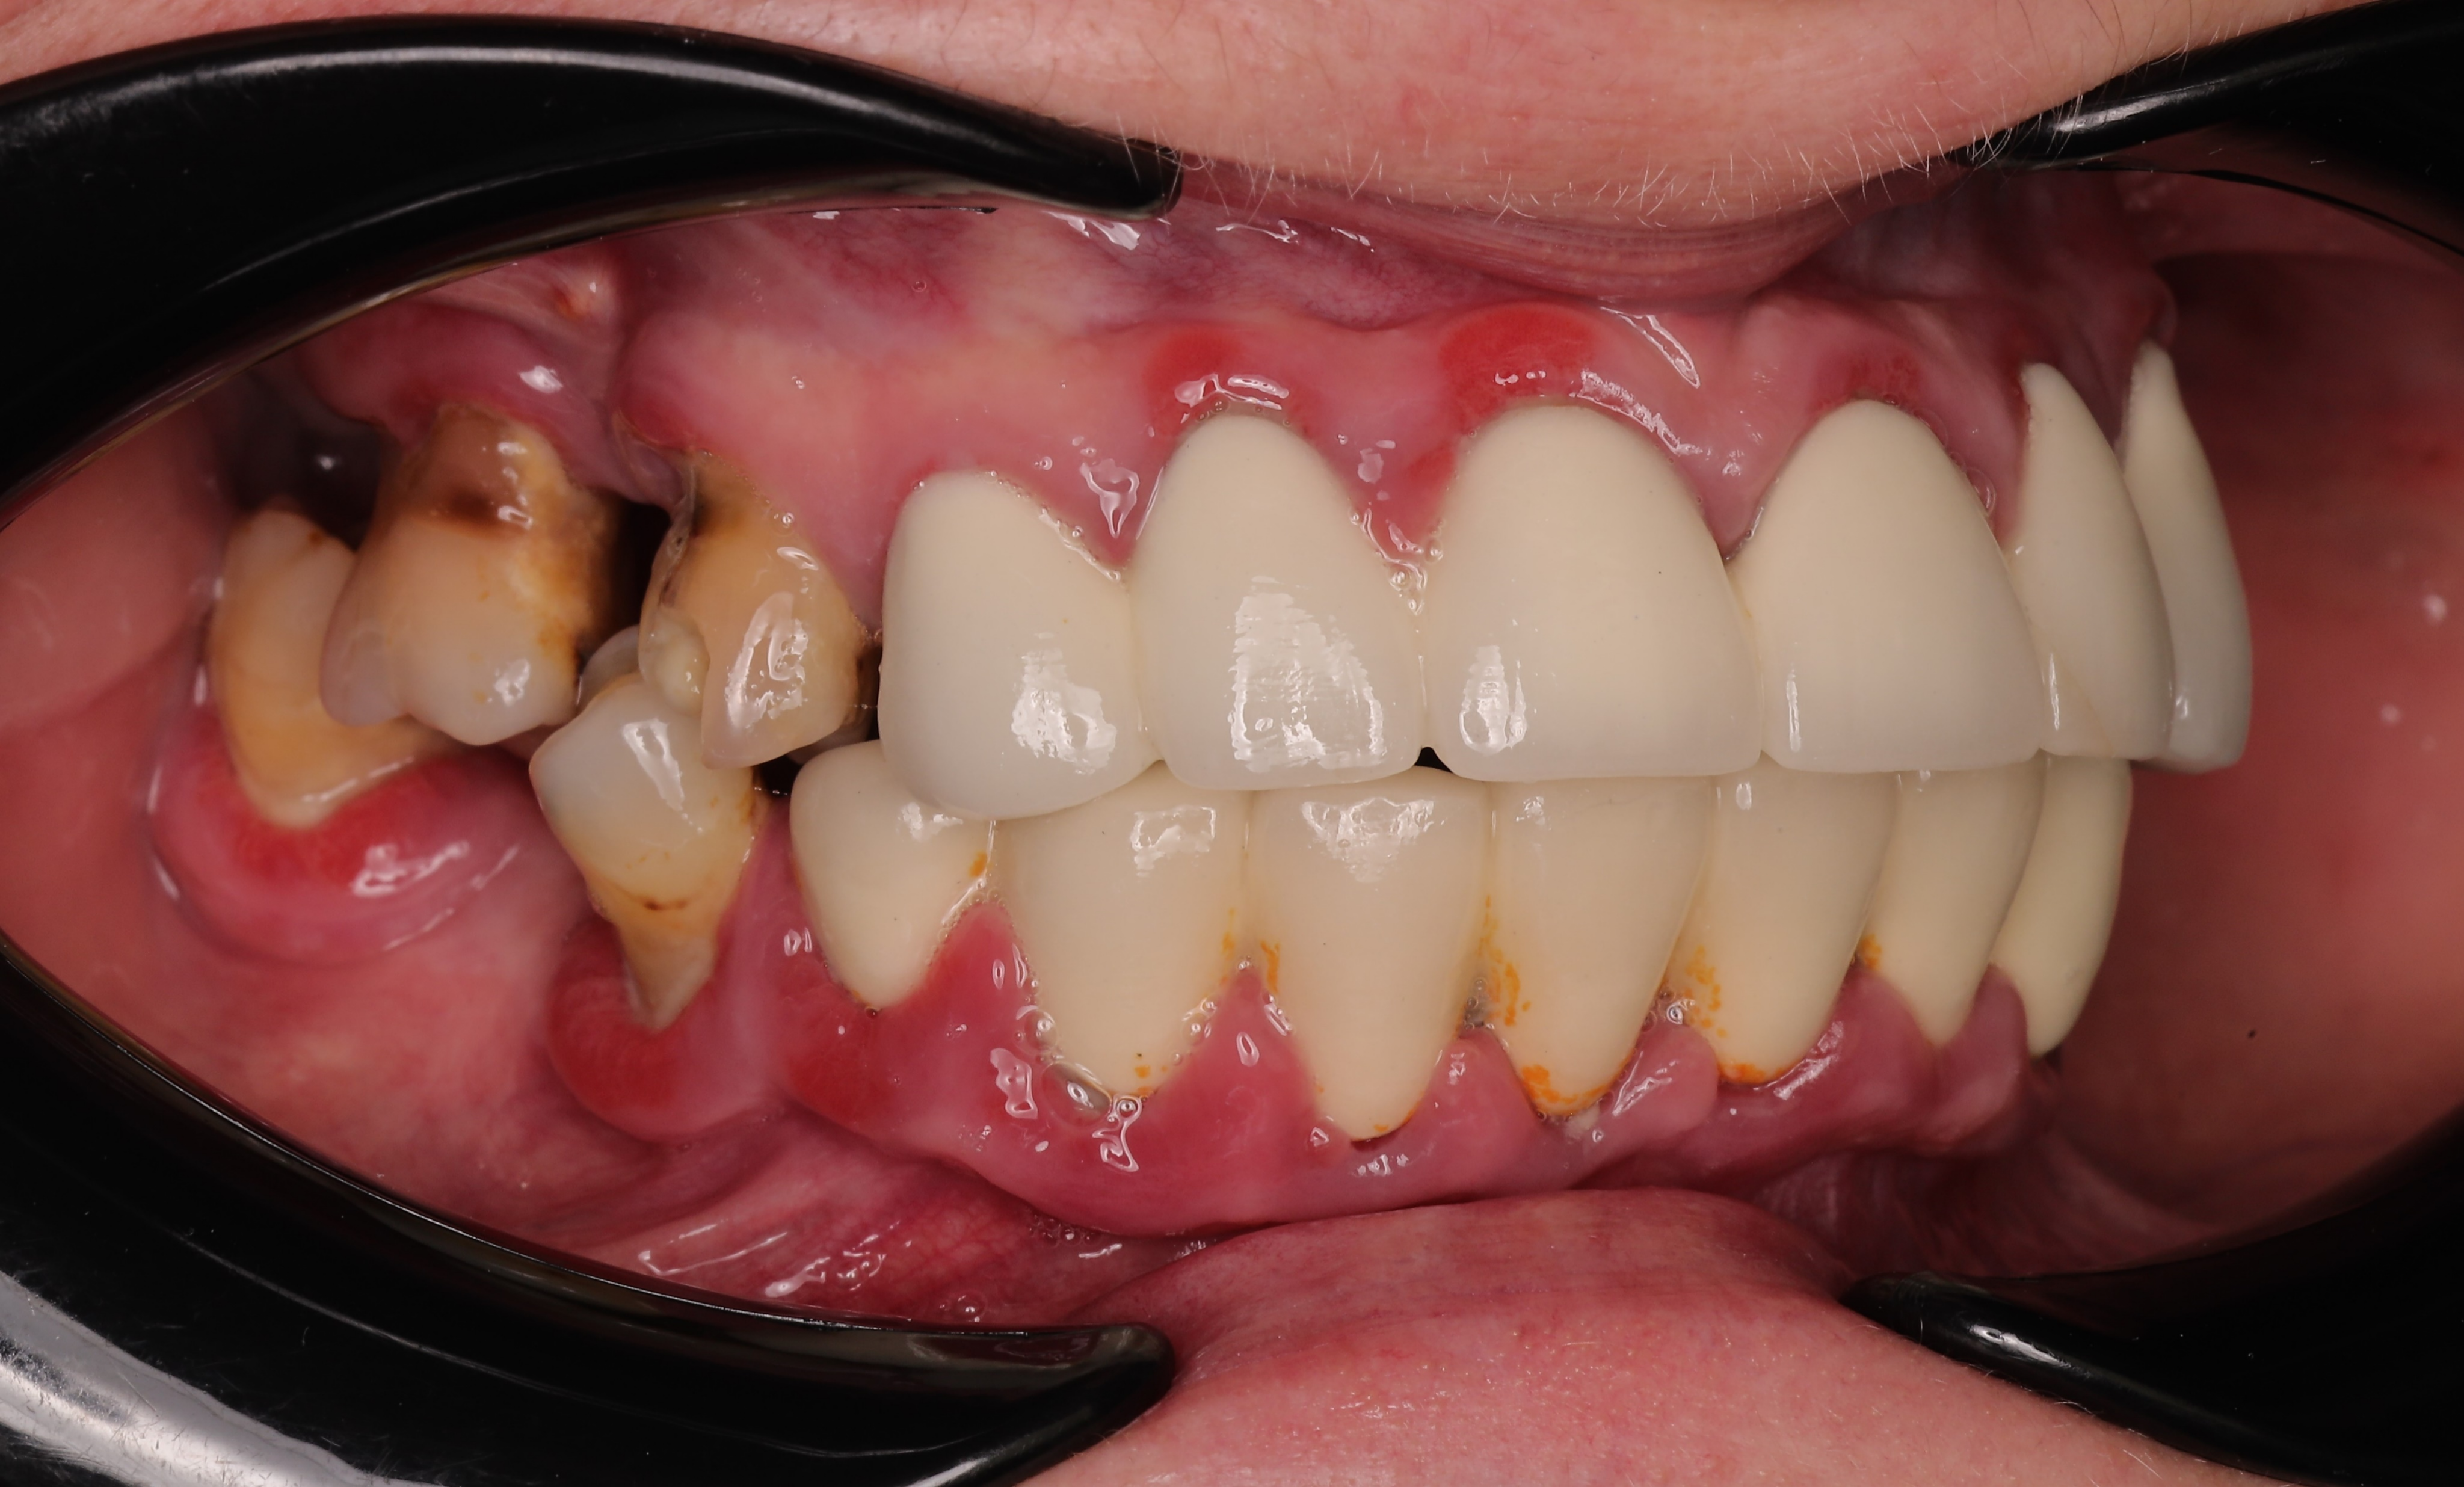

A 52-year-old female with Type II diabetes presented with failing dentition, characterized by generalized mobility, gingival bleeding, and poorly fitting dentures. Clinical challenges included arch deformities and severe posterior maxillary bone deficiency due to advanced sinus pneumatization. To meet the patient's request for immediate function and esthetics, a "teeth-in-a-day" protocol was implemented, involving full-arch extractions, IPG scanning, immediate implant placement, and the delivery provisional restoration on the day of surgery.